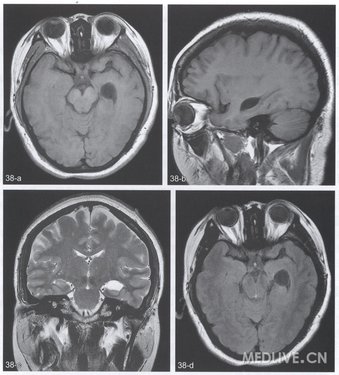

【CT与MRI所见】左侧颞叶内侧的海马与间脑之间椭圆形T1WI低信号及T2WI高信号病变,FLAIR序列呈低信号,大小为3cm×2cm×2.8cm,边缘清楚,灶周无水肿,邻近脑实质受压(图38a~d)。

【影像学特点】影像学特点为海马、间脑及中脑之间边缘清楚的圆形或椭圆形,甚至梭形的脑脊液样病变,邻近脑实质可见受压移位,但无灶周水肿。CT表现为均匀水样密度,无钙化,注射对比剂后无强化。典型MRI表现为类似脑脊液信号的T1WI低信号及T2WI高信号的囊状病变,边缘清楚,FLAIR序列为低信号,DWI图像上扩散无受限。无瘤周水肿、胶质增生等征象。增强T1WI上囊壁及囊内均无强化,但可见强化的颞角脉络丛受压变形。